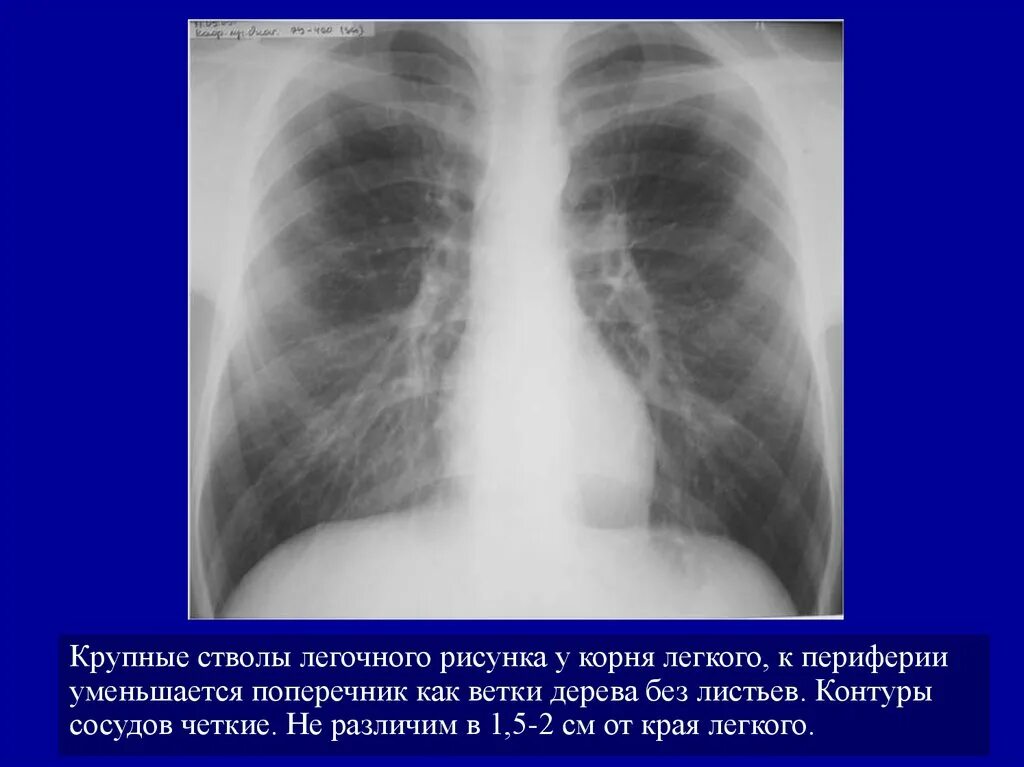

Легочный ствол легкого